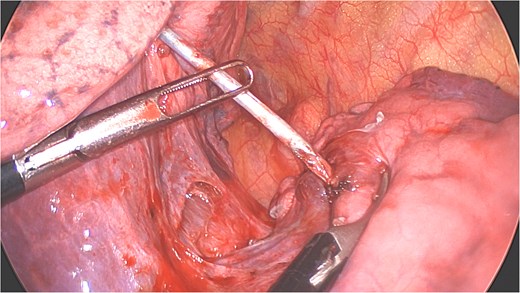

A clear minor pleural effusion and translucent scissural and para-aortic adhesions were visible. The adhesions of the pulmonary apex were released but no abnormality of the parietal pleura nor bone was visible. As the lung then collapsed, the pin became spontaneously visible protruding in the main fissure. As expected, the proximal part was in segment 2 and the distal half inside the apical segment of the lower lobe (S6) but it did not protrude outside of the parenchyma on either side (Fig. 4). The K-wire was easily removed by gently pushing back the parenchyma towards both extremities (Fig. 5). The pin seemed to be surrounded by a fine membrane that was coagulated at the visceral pleural entry point.

Extraction of the K-wire by pushing the parenchyma towards both extremities.